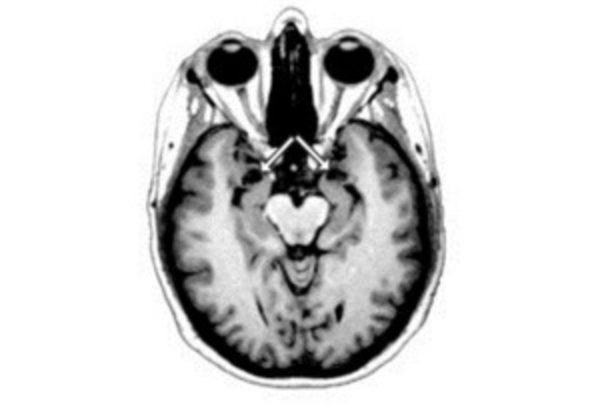

Группа ученых под руководством Алистэра Бушана из Оксфордского университета изучали процессы, которые происходят в клетках мозга во время инсульта. В ходе исследования ученые пытались продлить жизнь нейронов на как можно больший период.

Нейробиологи обратили внимание на то, что некоторые области мозга, например, "центр памяти", гораздо меньше страдают от отсутствия доступа к кислороду, чем другие его ткани.

Чтобы выяснить причину устойчивости клеток гиппокампа, ученые проследили за изменениями в химическом составе нейронов при наступлении инсульта. Как оказалось, через мгновения после прекращения доступа к кислороду и питательным веществам клетки начинают выделять большое количество белка гамартина, который обычно используется организмом для защиты мозга от развития раковых опухолей.

В случае с инсультом гамартин действует по-другому: его повышенная концентрация заставляет клетки расщеплять обрывки белков и "съедать" ненужные части клеток, извлекая из них энергию.

Ученые считают, что именно этот процесс помогает клеткам выживать при инсульте - нейроны мышей с "отключенным" геном, отвечающим за производство гамартина, погибали гораздо быстрее, чем нервные клетки нормальных грызунов.